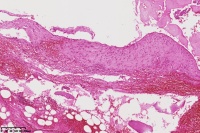

右胫骨内组织,单纯性骨囊肿?

性别

男

年龄

12岁

临床诊断

内生性软骨瘤?骨囊肿?

标本名称

右胫骨内组织

图2